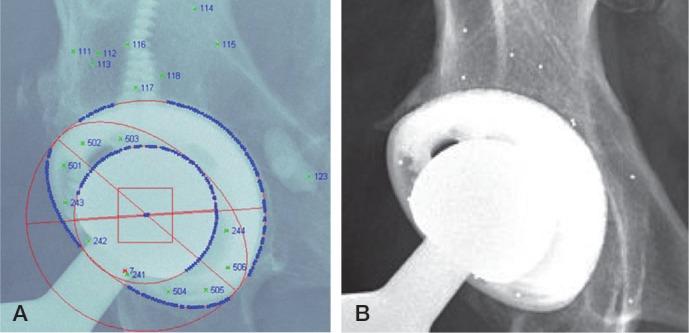

In traditional radiostereometric analysis (RSA), 1 segment defines both the acetabular shell and the polyethylene liner. However, inserting beads into the polyethylene liner permits employment of the shell and liner as 2 separate segments, enabling distinct analysis of the precision of 3 measurement methods in determining femoral head penetration and shell migration.

The UmRSA program was used to analyze the double examinations of 51 hips to determine if there was a difference in using the shell-only segment, the liner-only segment, or the shell + liner segment to measure wear and acetabular cup stability. The standard deviation multiplied by the critical value (from a t distribution) established the precision of each method.

Due to the imprecision of the automated edge detection, the shell-only method was least desirable. The shell + liner and liner-only methods had a precision of 0.115 mm and 0.086 mm, respectively, when measuring head penetration. For shell migration, the shell + liner had a precision of 0.108 mm, which was better than the precision of the shell-only method. In both the penetration and migration analyses, the shell + liner condition number was statistically significantly lower and the bead count was significantly higher than for the other methods.

Insertion of beads in the polyethylene improves the precision of femoral head penetration and shell migration measurements. A greater dispersion and number of beads when combining the liner with the shell generated more reliable results in both analyses, by engaging a larger portion of the radiograph.